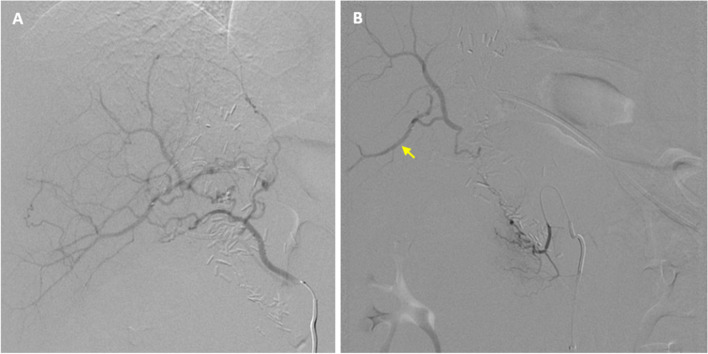

Case presentation: A patient presented with an enlarging hematoma due to bleeding at the gastroduodenal artery HAIP catheter insertion site. Emergent angiography revealed concomitant common hepatic artery occlusion and retrograde perfusion of the GDA via tortuous, diminutive hepatic collaterals which precluded standard antegrade approach. Collateral inflow from the dorsal pancreatic artery was utilized to opacify the right hepatic artery. The segment 5 hepatic artery was percutaneously accessed under fluoroscopic guidance, and microcoils were deployed both proximal and distal to origin of the gastroduodenal artery. The patient remained stable throughout the postoperative period and was discharged after an otherwise uneventful admission. Follow-up computed tomography demonstrated resolution of the hematoma and no bleeding or biliary complication from transhepatic access.